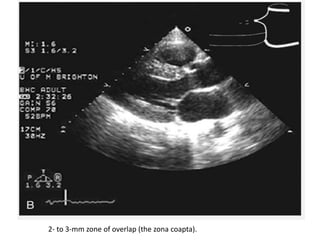

2- to 3-mm zone of overlap (the zona coapta).

2- to 3-mmzone of overlap (the zona coapta).

• 25.

• #27 Apical four-chamber view recorded in systole in a normal patient. In this image, the normal closure pattern of the anterior and posterior leaflets of the mitral valve is clearly demonstrated. At the upper right, the closure pattern has been expanded. Note that the anterior and posterior mitral valve leaflets do not close tip to tip but rather along a 4-mm length [the zona coapta (ZC)].